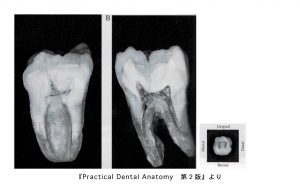

下顎第一大臼歯の中身

• 歯の外形を縮小した形。

• 髄室角は近心側ほど鋭く突出。近心舌側は近心頬側より鋭く、高く突出している。

• 根管数は2〜4根管

• 近心根は頬舌的に分岐した2根管性(80%)が多く、遠心根は1根管性(70%)が多く認められる

• 根尖孔付近は強く狭窄されて細く、小さく彎曲していることが多い。